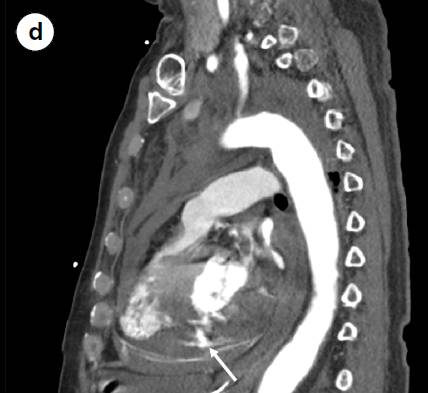

a 心电图显示Ⅱ、Ⅲ、aVF导联出现ST段抬高及Q波。 b 轴位CT扫描图像显示造影剂渗漏到心包、纵隔(三角形箭头)以及左侧胸腔的血性积液中(长箭头)。冠状位(c)和矢状位(d)CT重建显示造影剂从左心室向心包渗漏(长箭头)和右心室壁相对比的低密度影(三角形箭头)。